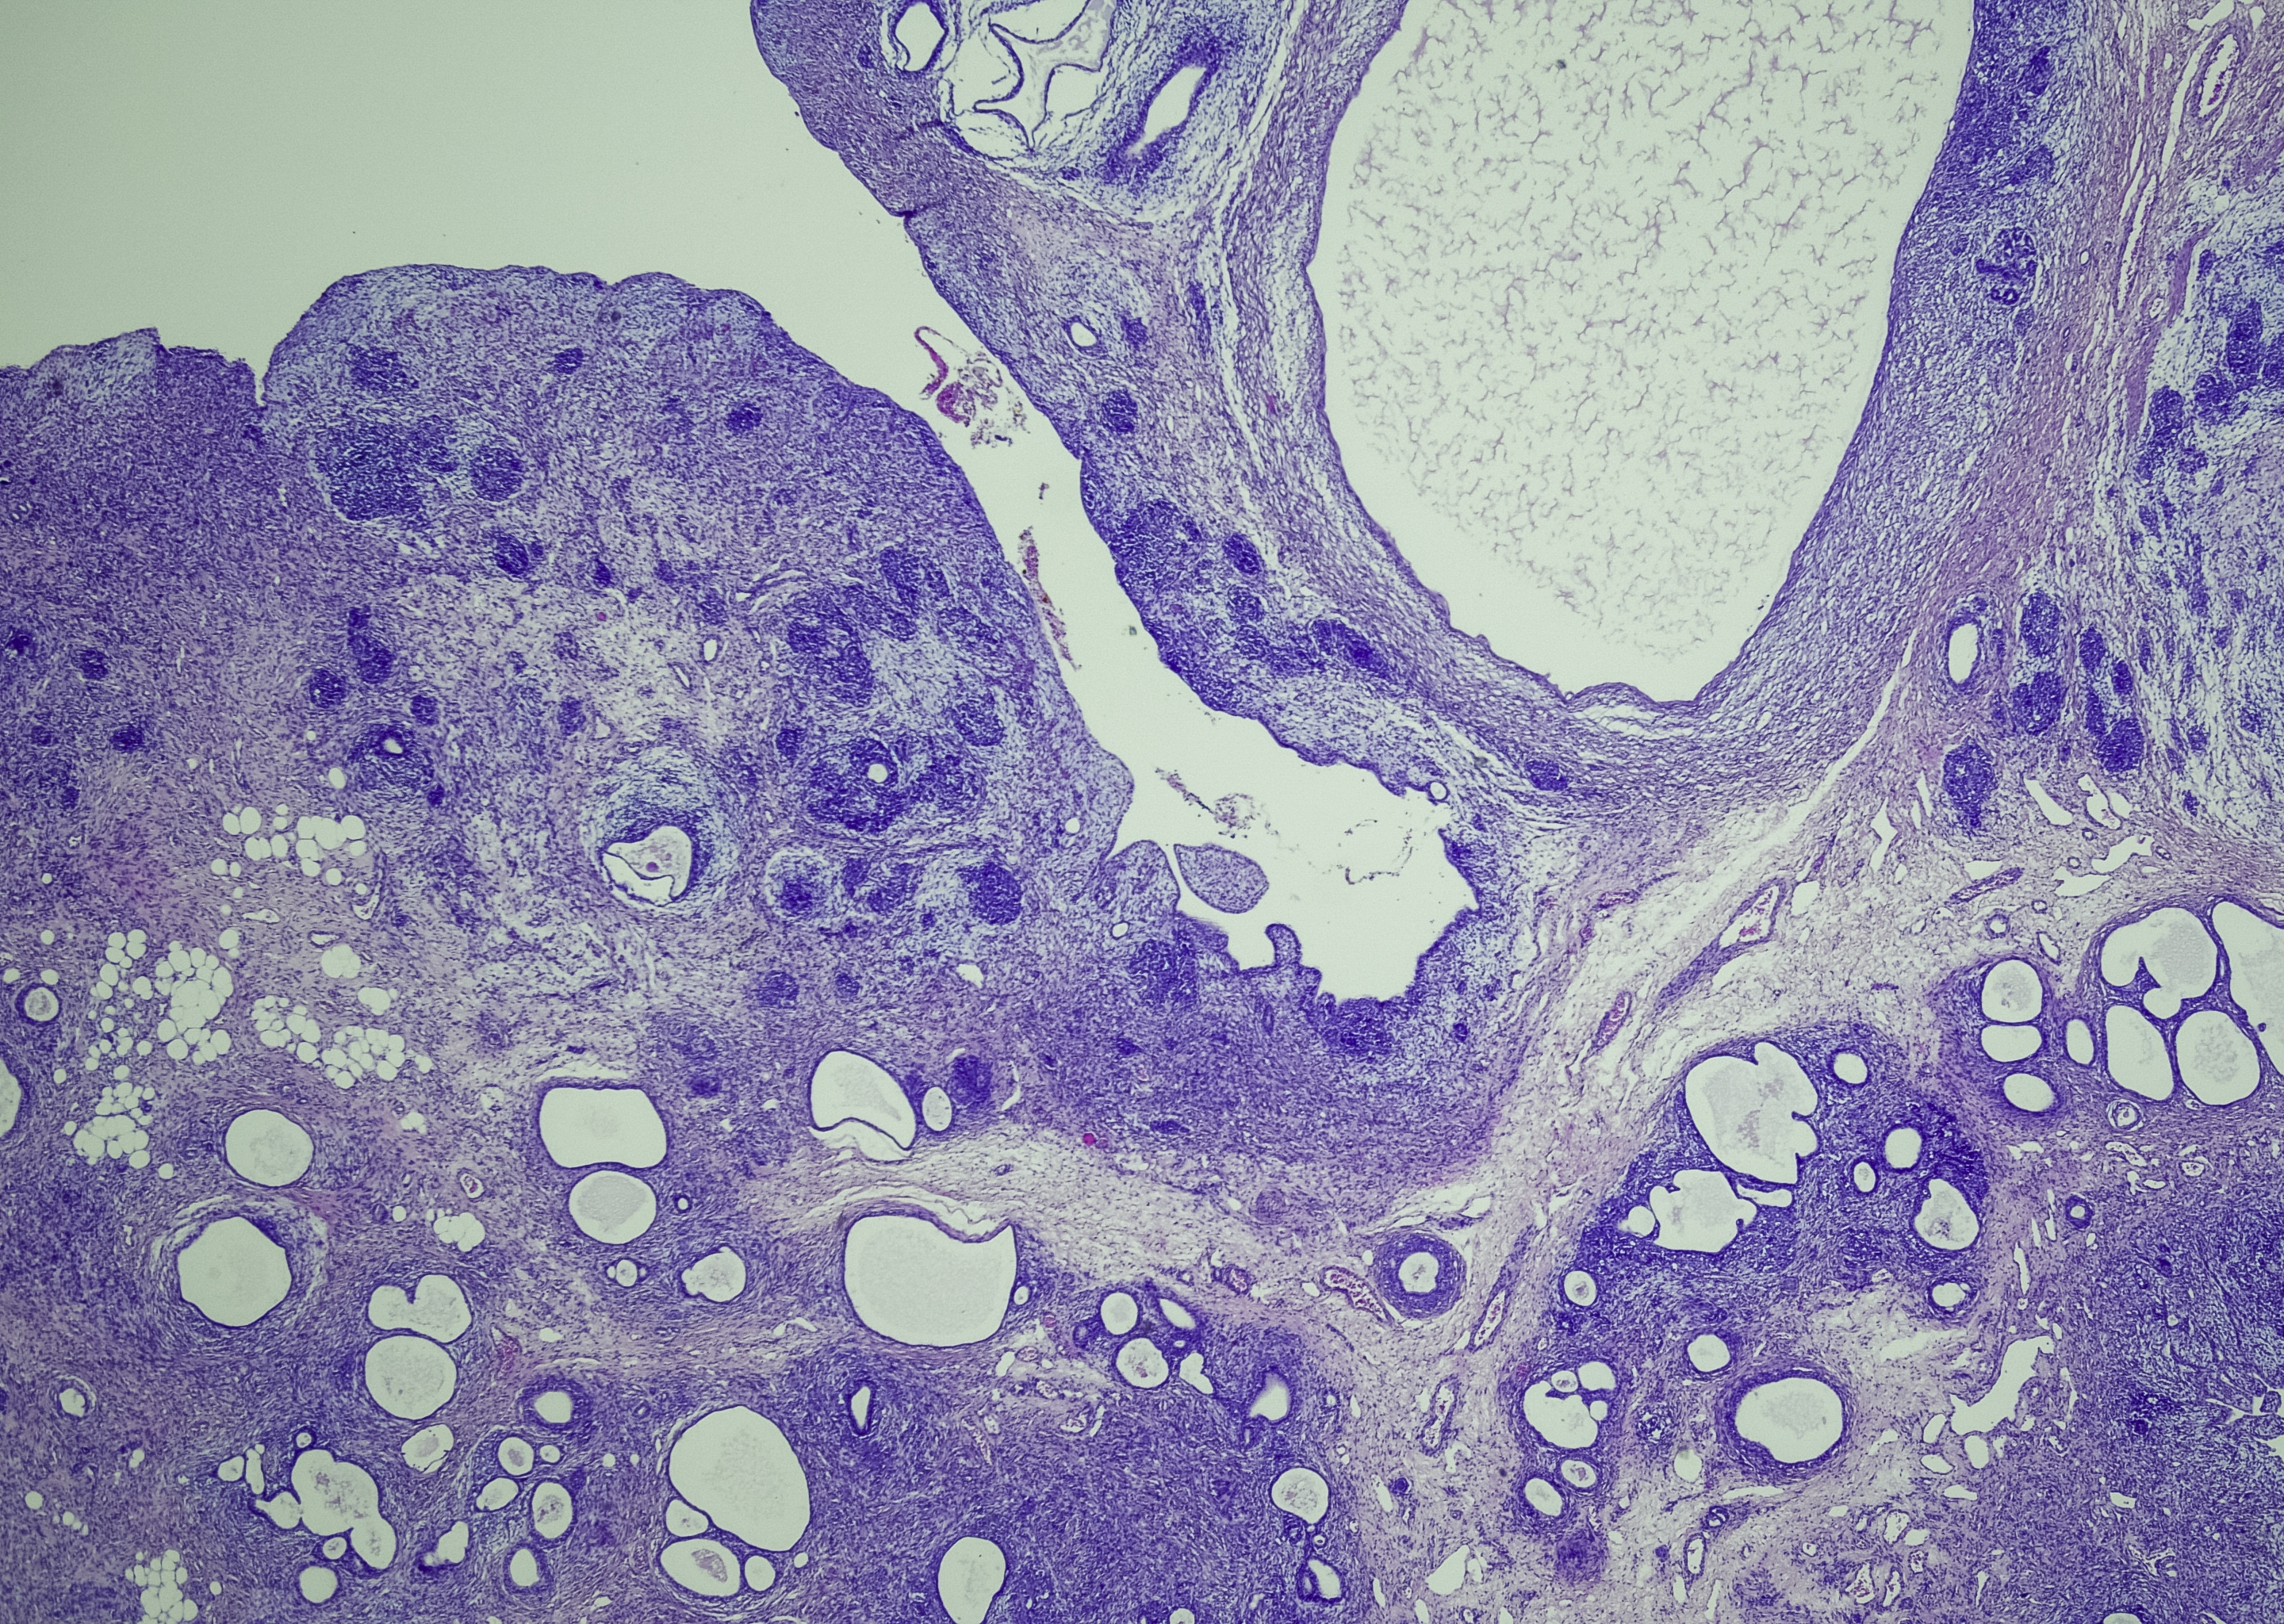

Wilms’ Tumour is a type of Kidney Cancer and comes from very specialised cells which are involved in the development of a baby’s kidneys while the baby is still in the womb. The cells usually disappear at birth but in children with this cancer, cells (nephrogenic rest cells) will remain.